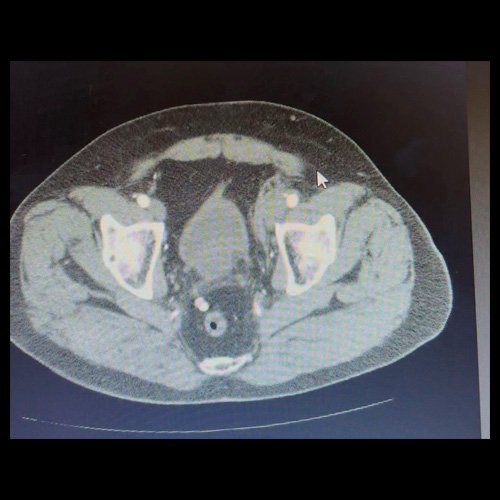

• AngioTAC de miembros inferiores (Día 2): Ateromatosis parietal calcificada parcheada en todo el territorio aorto-ilíaco-femoral bilateral. LADO DERECHO: Arteria ilíaca interna: de calibre y trayecto conservado, permeable. Arterias ilíaca externa y femoral común: de calibre y trayecto conservados, permeables. Arterias circunfleja ilíaca superficial y epigástrica superficial: de calibre y trayecto conservados, permeables. Arteria femoral superficial: de calibre y trayecto conservado, permeable. Arteria femoral profunda: de calibre y trayecto conservado, permeable. Arterias circunflejas femoral medial y lateral: de calibre y trayecto conservados, permeables. Arteria poplítea: de calibre y trayecto conservado, permeable. Arteria tibial anterior: de calibre y trayecto conservado, permeable. Arteria tibial posterior: de calibre y trayecto conservado, permeable. Vena ilíaca primitiva: 13 mm, vena ilíaca externa 11 mm, vena ilíaca interna 7 mm. LADO IZQUIERDO: En esta ocasión, en fase angiográfica se observa de calibre y opacificación conservada de las arterias femoral superficial y profunda, poplítea y de sus ramas musculares en muslo y pierna. En fase venosa se evidencia un defecto de relleno endoluminal de la vena primitiva izquierda que impresiona extenderse actualmente a la vena iliaca externa, a la vena femoral superficial y poplítea, hasta nivel del hueco homonimo, las cuales se visualizan aumentadas de calibre con respecto a sus contralaterales, en relación a trombosis venosa profunda. Se sugiere cotejar con ecodoppler de miembros inferiores. No se identifica compromiso de la porción visualizada de la vena cava inferior ni del sistema venoso ilíaco contralateral. Se visualiza dispositivo vascular en VCI (filtro VCI), infrayacente a las venas renales. Presenta aumento del diámetro del muslo izquierdo con respecto a su contralateral, asociado a edema de los tejidos blandos superficiales. Reticulación de la grasa de la región inguinal a predominio izquierdo con algunas burbujas aéreas. Se observa inmediatamente infrayacente a los antes mencionado, un área hiperdensa que realza en fase venosa, con centro hipodenso, que mide 2.2 cm x 1.4 cm, ya visualizado en tomografía previa. Cambios artrodegenerativos coxo-femorales y tricompartimentales en la rodilla. Signos de entesopatía cuadricipital distal. No se observan alteraciones a nivel del fémur ni de las porciones visualizadas de la tibia y el peroné. Arteria ilíaca interna: de calibre y trayecto conservado, permeable. Arterias ilíaca externa y femoral común: de calibre y trayecto conservados, permeables. Arterias circunfleja ilíaca superficial y epigástrica superficial: de calibre y trayecto conservados, permeables. Arteria femoral superficial: de calibre y trayecto conservado, permeable. Arteria femoral profunda: de calibre y trayecto conservado, permeable. Arterias circunflejas femoral medial y lateral: de calibre y trayecto conservados, permeables. Arteria poplítea, tibial anterior y tibial posterior: de calibre disminuido con respecto a su contralateral, permeables. Vena ilíaca primitiva: 14 mm, vena ilíaca externa 17 mm, vena ilíaca interna 9 mm. Calcificaciones en conducto inguinal bilateral. Hidrocele bilateral.

• TAC de abdomen y pelvis con contraste EV (Día 10): El hígado es de forma, tamaño y situación habituales. Su superficie es lisa, y sus bordes son agudos. No presenta alteraciones densitométricas ni efectos de masa focales. La vía biliar intra y extrahepática es de calibre conservado. La vesícula biliar es de forma, tamaño y situación normales, sin imágenes que sugieran la presencia de litiasis. Tener en cuenta que este método puede pasar por alto litiasis colesterínicas. El bazo es de forma, tamaño y situación normales. El eje esplenoportal es de calibre y trayecto conservado. El páncreas es de características normales. El conducto de Wirsung es de calibre conservado. Las glándulas adrenales son normales. Ambos riñones son de forma, tamaño y situación habituales. Sin evidencia de alteraciones calicopiélicas ni ureterales. Quistes simples corticales en riñón izquierdo, el mayor de ellos en polo superior, que mide 16 mm. Discreta reticulación de la grasa perirrenal bilateral. La aorta, las arterias ilíacas primitivas, internas, externas y femorales, son de calibre y trayecto conservado. La vena cava inferior y las venas ilíacas primitivas, internas, externas y femorales son de calibre y trayecto conservados. Filtro de vena cava inferior infrayacente a venas renales. No se observan adenomegalias intraperitoneales, retroperitoneales, ilíacas ni inguinales. No se observan alteraciones a nivel del tracto gastrointestinal. Abundante contenido de materia fecal en el colon. Vejiga con escasa repleción. La próstata y las vesículas seminales son de características normales. No se observa líquido libre ni neumoperitoneo Presenta aumento del diámetro de la raíz del muslo izquierdo con respecto a su contralateral, asociado a edema de los tejidos blandos superficiales. Reticulación de los tejidos blandos de la región inguinal izquierda, de mayor jerarquía que en estudio anterior, con tendencia a coleccionar. Además se observan ganglios locorregionales aumentados en número y tamaño sin alcanzar rango megálico. Se observa inmediatamente infrayacente a los antes mencionado, un área hiperdensa que realza en fase venosa, con centro hipodenso, que mide 2.2 cm x 1.4 cm, ya visualizado en tomografía previa, sin cambios. Calcificaciones en conducto inguinal bilateral. Hidrocele bilateral. Marcados cambios artrodegenerativos de la columna lumbosacra y coxo-femorales.

Angio TAC de miembros inferiores (Día 2)